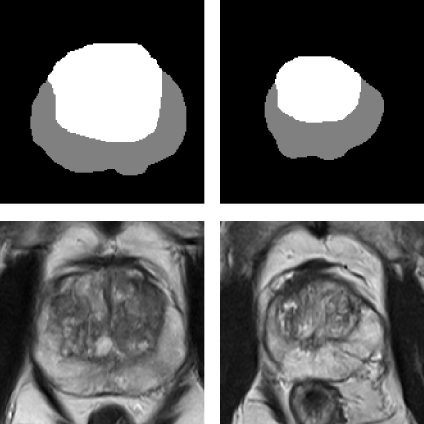

Bashkanov, O; Rak, M; Engelage, L; Hansen, C

@inproceedings{bashkanov_augmenting_2025,

address = {Cham},

abstract = {The need for artificial intelligence (AI)-driven computer-assist ed diagnosis (CAD) tools drives up the demand for large high-quality datasets in medical imaging. However, collecting the necessary amount of data is often impractical due to patient privacy concerns or restricted time for medical annotation. Recent advances in generative models in medical imaging with a focus on diffusion-based techniques could provide realistic-looking synthetic samples as a supplement for real data. In this work, we study whether synthetic volumetric MRIs generated by the diffusion model can be used to train downstream models, e.g., semantic segmentation. We can create an arbitrarily large dataset with ground truth by conditioning the diffusion model with a segmentation mask. Thus, the additional synthetic data can be used to control the dataset diversity. Experiments revealed that downstream tasks profit from additional synthetic data. However, the effect will eventually diminish when sufficient real samples are available. We showcase the strength of the synthetic data and provide practical recommendations for using the generated data in zonal prostate segmentation.},